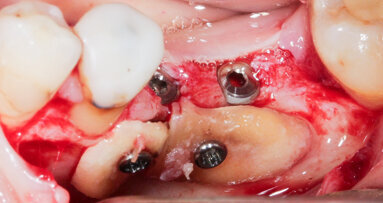

Nicméně, štěp je nutno zcela imobilizovat a zakrýt granulátem. Zpočátku jsem při horizontálních i vertikálních augmentacích používal nevstřebatelné, titanem vyztužené membrány. Tyto membrány fungovaly dobře, ale někdy bylo velmi náročné je umístit a mnozí lékaři je nepřijali dobře. Vyvstala otázka: Proč nepoužívat zbývající kostní stěnu chytřejším způsobem? Začal jsem tedy s dobrými výsledky používat při horizontálních augmentacích vstřebatelné tuhé membrány. Dnes používám přírodní kolagenní membránu Geistlich Bio-Gide.

Připevnili jsme s týmem kolagenní membránu titanovými piny ke kostním stěnám a vyplnili prostor pod membránou tak, aby vznikl velmi stabilní štěp. Celý štěp vypadá jako hodně naplněná klobáska (pozn. redakce: sausage – klobása anglicky). Materiál Geistlich Bio-Gide působí v prvních týdnech hojení jako imobilizovaná „nacpaná“ tkáň ve tvaru klobásky.

Dosahujeme s touto technikou použití směsi materiálu Geistlich Bio-Oss a autogenních kostních částic v poměru 1 : 1 velmi předvídatelných výsledků. Obvykle odebereme pomocí kostních škrabek dostatek kosti na štěp. Částice Geistlich Bio-Oss se do štěpu dobře začlení a pomáhají zmírnit resorpci štěpu. To bylo dobře prokázáno jak klinicky, tak histologicky v naší nedávné sérii prospektivních případů.1

Materiál Geistlich Bio-Gide má všechny tyto vlastnosti. Absenci titanové výztuže lze spolehlivě překonat upevněním membrány z lingvální nebo palatinální a vestibulární strany. Dnes již používáme membrány vyztužené titanem výhradně u vertikálních defektů.

V posledních deseti letech jsem měl pouze jeden případ v distálním úseku dolní čelisti, při němž u pacienta vznikla pooperační infekce.1 Za tuto komplikaci mohu obviňovat jen sám sebe, protože je pravděpodobné, že infekce pocházela od třetího moláru, který jsem měl extrahovat. Každopádně, obecně je tato procedura velice úspěšná a předvídatelná. Pomocí této techniky můžeme rekonstruovat i zcela resorbované bezzubé hřebeny horní čelisti. Ale samozřejmě, klíčovými faktory, pokud jde o snížení míry výskytu jakýchkoli komplikací, je adekvátní příprava pacienta a pooperační management, stejně jako precizní chirurgické techniky.